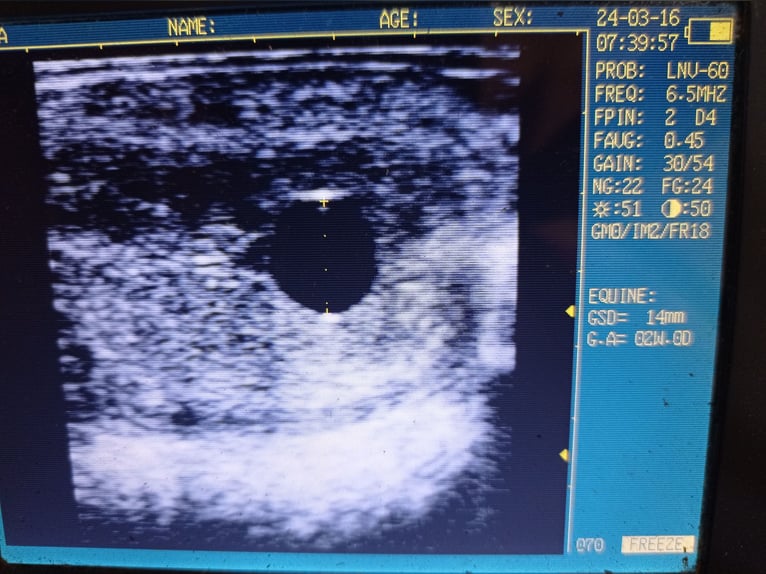

Pedigree and ultrasound picture in the pictures.

Pedigree y imagen de ultrasonido en las fotos.

Ascendance et échographie avec les photos.

Pedigree e foto ecografica con le immagini.

Stamboom en echo in de foto's.

Rodowód i zdjęcie USG na zdjęciach.

Stamtavla och ultraljudsbild i bilderna.